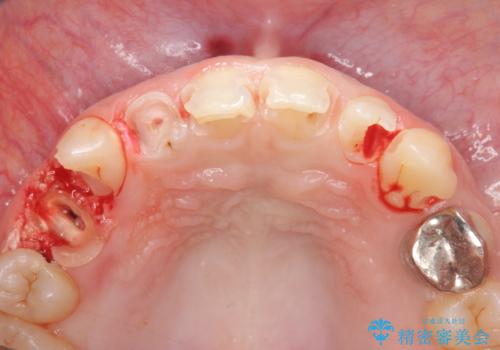

- 放置した虫歯の歯がボロボロになってしまい治療を希望され来院されました。

残根状態の歯、神経まで虫歯が達し失活した歯、歯肉縁下まで及んだ虫歯が多数認められます。

まず虫歯を拡大鏡、マイクロスコープ下で丁寧に取り除き歯肉縁下の虫歯を歯周外科により解決したのち、ジルコニアクラウン製作を行っていきます。